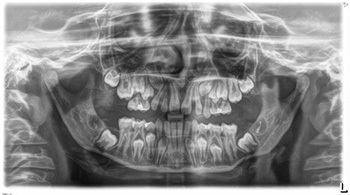

An 11-year-old patient was referred by a pediatric dentist for orthodontic evaluation with several unusual findings: microdontia, severe developmental delay in eruption, and several positional concerns. Clinical and radiographic examination revealed a retained tooth in the upper right quadrant, suspected to be either a primary tooth or a supernumerary permanent lateral. The upper right first molar was ectopic, appearing to be “caught” beneath the retained tooth, and the upper left first molar had not erupted at all. Additional findings included a full posterior right crossbite and evidence of overall dental delay compared with age norms (Figs. 1–3).

Fig. 1

One point of discussion was the nature of the retained upper right tooth. On closer inspection of the radiographs, several practitioners suggested that the tooth resembled a supernumerary permanent lateral rather than a retained primary, given the similarity in root morphology between the two teeth present in that area. Regardless of its classification, the consensus was that the tooth should be removed, as it was interfering with eruption of the adjacent permanent molar and could complicate arch development if left untreated.